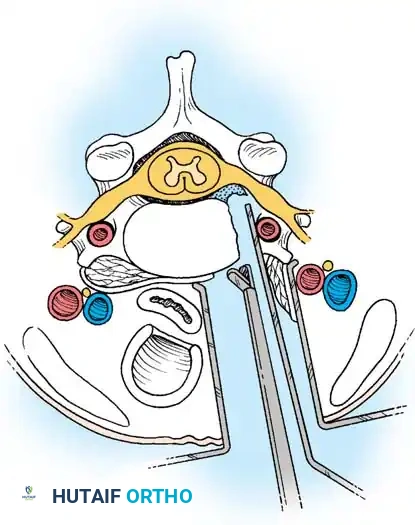

The anterior approach utilizes the avascular plane between the visceral neuraxis (trachea/esophagus) and the vascular neuraxis (carotid sheath).

Step 1: Exposure and Retraction

Following a transverse incision within a natural skin crease (usually left-sided to protect the recurrent laryngeal nerve, which has a more predictable course on the left), the platysma is divided. The deep cervical fascia is incised anterior to the sternocleidomastoid. Blunt dissection separates the carotid sheath laterally from the trachea and esophagus medially. The prevertebral fascia is incised to expose the longus colli muscles.

Posterior Cervical Foraminotomy

Foraminotomy is highly effective for unilateral radiculopathy caused by a lateral soft disc herniation or isolated foraminal stenosis, avoiding the morbidity of an anterior fusion.

Step 1: Posterior Exposure

The patient is positioned prone, often using a Mayfield head holder. A midline posterior incision is made, and the paraspinal musculature is subperiosteally elevated off the spinous processes and laminae on the symptomatic side.